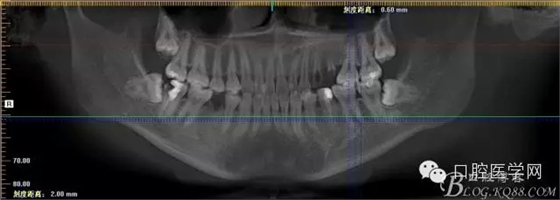

補(bǔ)拍CBCT進(jìn)行診斷分析

CBCT測量得出根尖囊腫3×4mm,進(jìn)行常規(guī)根管充填后行根尖切除術(shù)